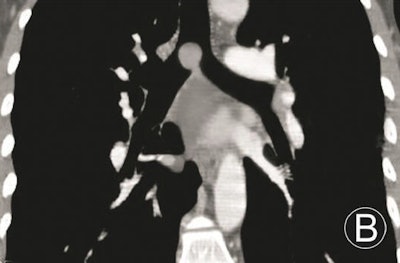

The results demonstrated that MPR could not only display the locations, morphologies, internal features, and extramural invasions of primary trachea and main bronchus tumors, along with morphologies and extents of luminal stenoses, it could also measure their longitudinal involvement and distances between main bronchus tumors and trachea carinae. However, due to the 2D images, MPR could not provide a 3D effect, according to the researchers.

Volume-rendered images can handily demonstrate locations, morphologies of primary trachea and main bronchus tumors, and morphologies and extents of luminal stenoses, and it can measure the longitudinal involvements and distances between main bronchus tumors and trachea carinae. However, volume rendering can't display the internal features of tumors and extramural invasions, they noted.